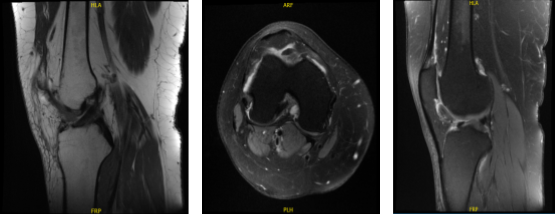

Which showed lateral tilt of the patella towards the trochlea along with advanced patellofemoral arthritis with mild medial compartment arthritis. Also, the MRI was done to confirm the findings.

MRI-3T Right knee non-contrast